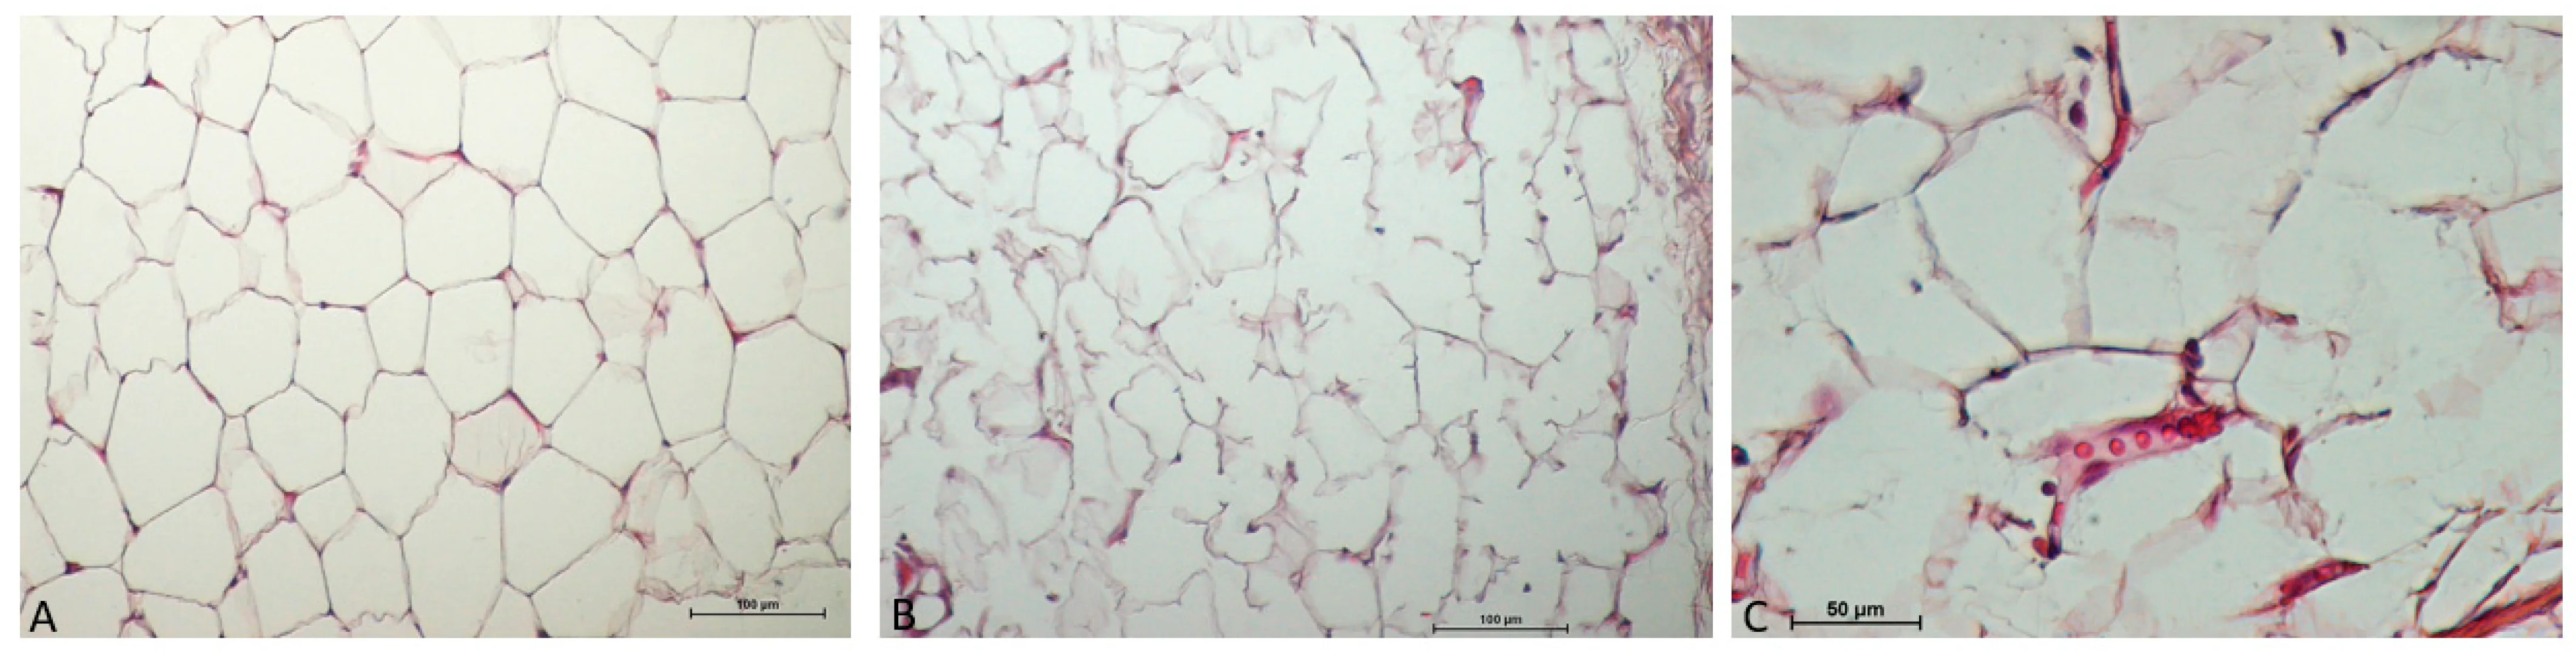

지방세포 사멸 유도

바디 온다리프팅 시술 직후 지방 세포막에 균열이 생기면서 세포 사멸이 발생합니다.